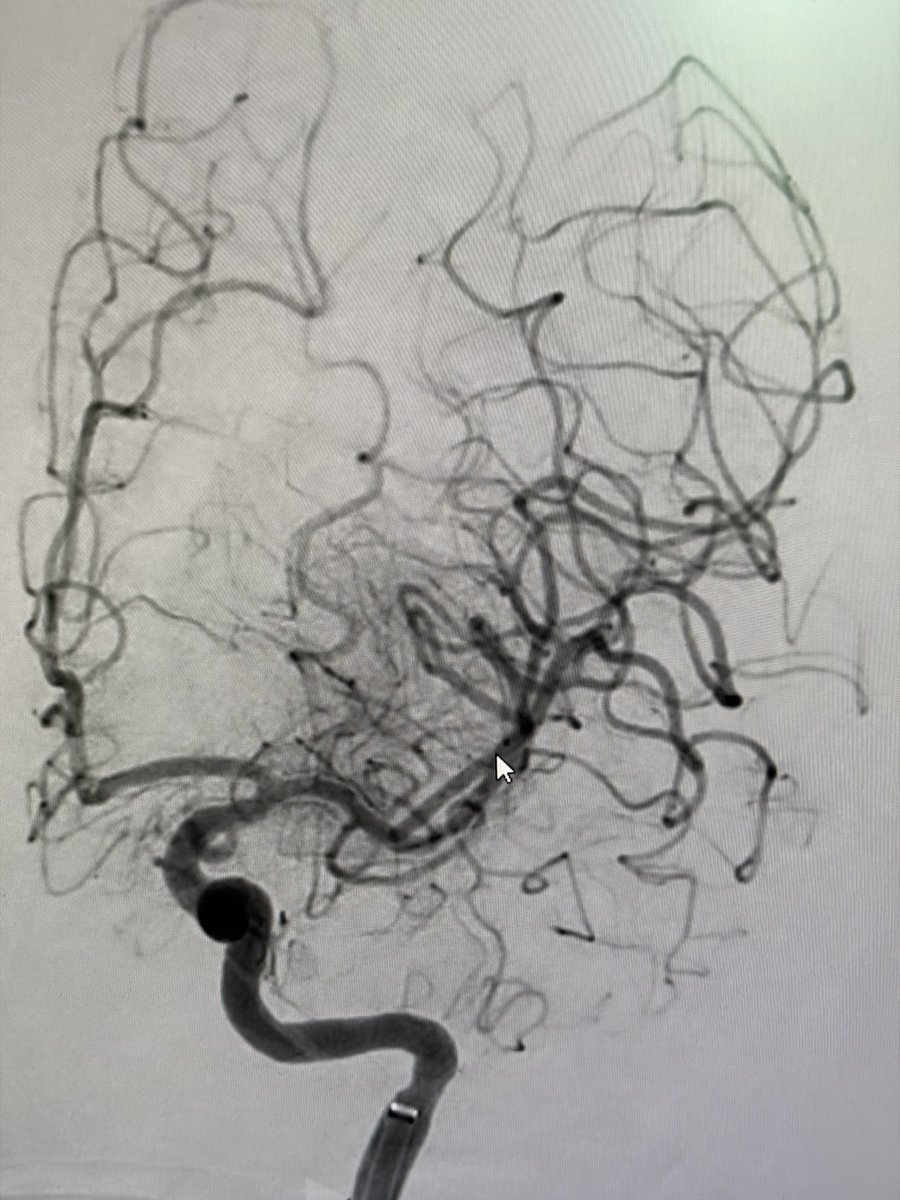

Recurrent hematuria in a 20yo patient solved! CT angiogram found a small renal AVM, which we successfully embolized using Onyx LES. Precise, organ-sparing treatment leading to rapid recovery. This is the power of Interventional Radiology! #AVM #Embolization #IR #KidneyHealth